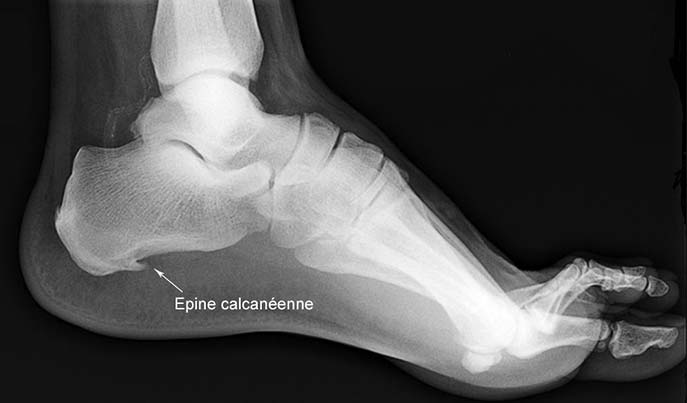

La réaction osseuse : les épines calcanéennes

Face aux tensions chroniques du fascia plantaire, l’os du talon réagit en formant des excroissances osseuses, appelées épines calcanéennes ou « spurs ». Ces dépôts de calcium au talon cherchent probablement à renforcer l’insertion du fascia plantaire.

Les épines calcanéennes sont donc secondaires à la fasciite plantaire dans la majorité des cas. Elles aggravent la douleur en irritant les tissus mous environnants. Heureusement, elles finissent par se résorber spontanément une fois les tensions du fascia apaisées.

Des examens d’imagerie permettent de compléter le diagnostic :

- La radiographie met en évidence d’éventuelles épines calcanéennes.